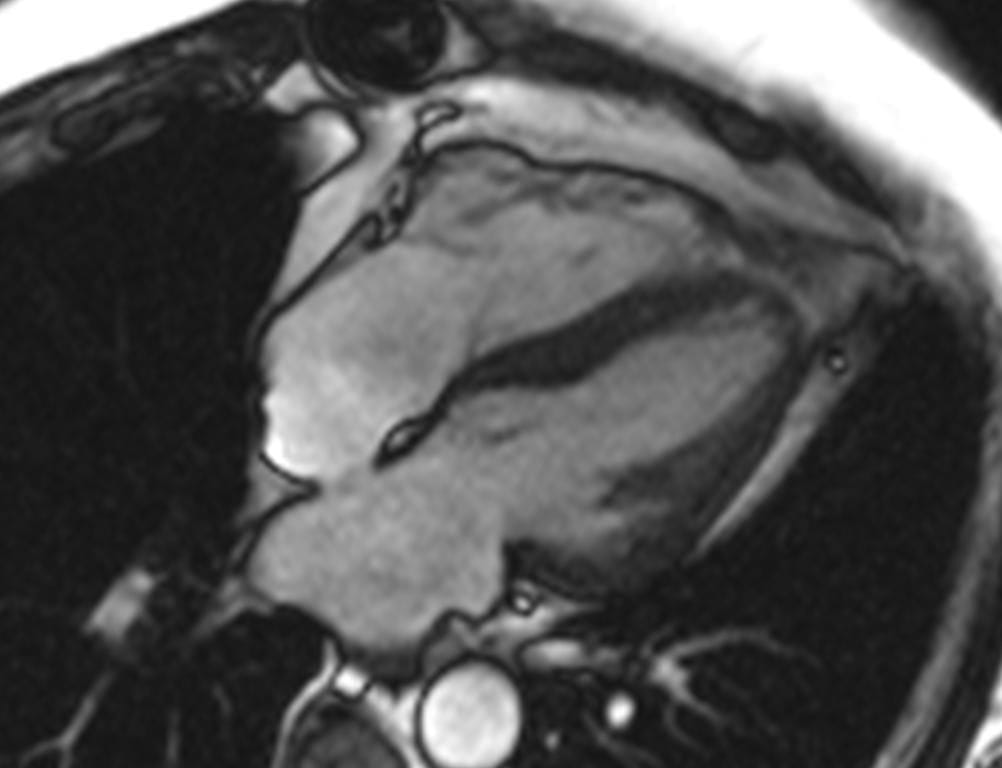

Cardiac MR scan Cardiac MR image.

Sophisticated imaging, combined with exercise physiology and analysis of inflammation, will extend the understanding of persistent myocardial fibrosis and edema and the activation of fibrotic and inflammatory pathways. The trial will utilize cardiovascular MRI to characterize the myocardium and define edema and diffuse fibrosis.